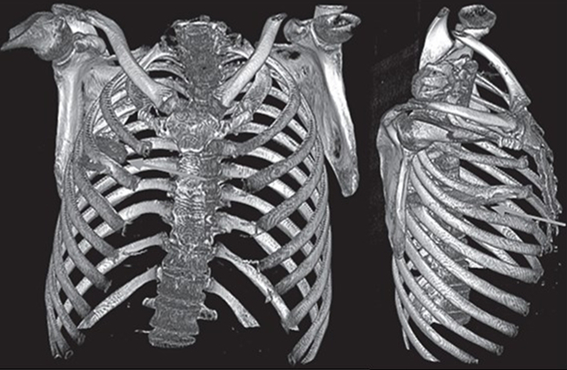

Incredibly, a chest radiograph found the cause of his current ailment – a large knife blade lodged in the mid-thorax.

Doctors could see the knife had entered through the right scapula, and had managed to dodge any major organs.